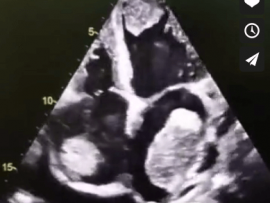

Lee mas45 years old female patient with congestive Heart Failure “EF=22%” and history of stroke , the Echocardiography shows multiple big thrombi in the Heart chambers and moderate pericardial effusion ..